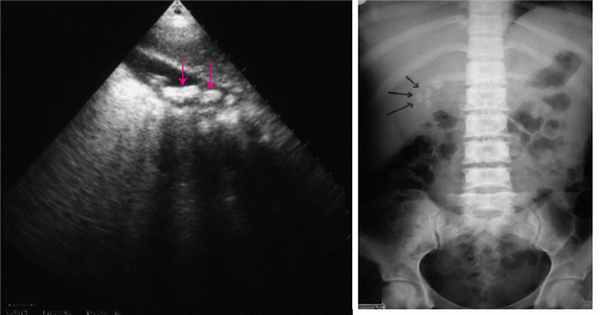

Дивертикулом называется мешковидное выпячивание слизистой и подслизистой оболочек полого органа.

Дивертикулы желудка в 75% случаев возникают на его задней стенке вблизи малой кривизны (обычно на расстоянии 2 см от пищеводно-желудочного соединения).

Наиболее часто дивертикулы локализуются в кардиальном и субкардиальном отделах желудка (почти в 80 % случаев), особенно на задней стенке. Значительно реже дивертикулы располагаются по большой кривизне (около 8%) и в антральном отделе (около 10%), очень редко (около 2%) - на передней стенке тела и по малой кривизне (в области средней и нижней третей желудка).

Дивертикулы имеют грушевидную, более редко - овальную или круглую форму. Размер ДЖ - в основном небольшой (2-3 см в диаметре), однако встречаются и ДЖ более крупных размеров (6-7 см и больше). В дивертикулах малых размеров обычно определяется мышечная оболочка, в средних ДЖ зачастую выявляются только отдельные мышечные пучки, в крупных - мышечная оболочка, как правило, отсутствует.